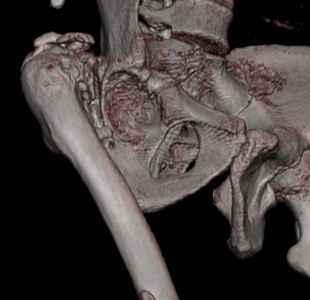

Пациент 30 лет 3 года назад в результате травмы получил травматический

дефект нижних конечностей до в/3 голеней, был пропущен вывих бедра. В настоящее время очень

неплохо ходит на протезах, движения в неоартрозе близки по объему к здоровой стороне.

Основная жалоба - выраженная боль при ходьбе. планируем двухэтапное эндопротезирование -

задним доступом мобилизовать проксимальный отдел бедра, резецировать шейку, аппаратом

низвести бедро(головку оставить там где она есть, так как больших дефектов не видно(может

пригодится в последующем?)). Вторым этапом бесцементное эндопротезирование. Насколько

такой вариант реалистичен? Доступ для второго этапа? Может быть, другие варианты?